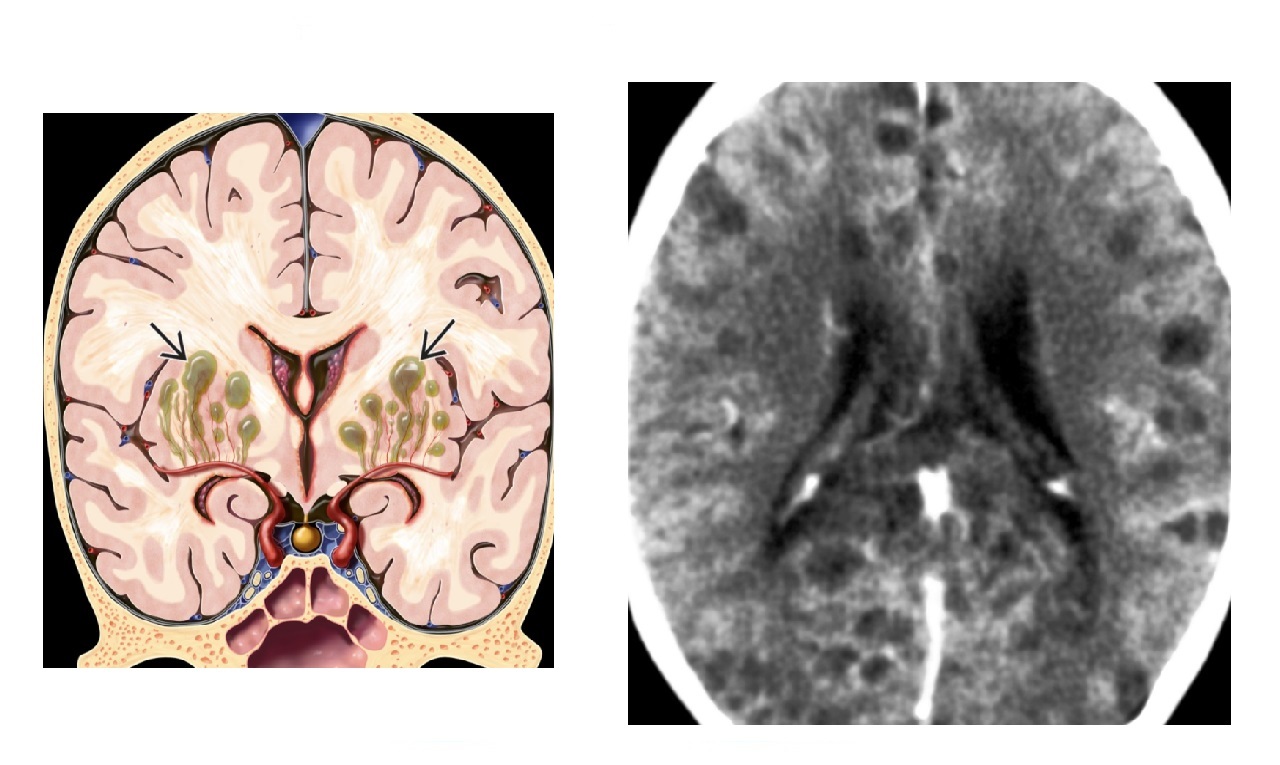

Tumours that ordinate from the ventricular wall?

Ependymoma Medulloblastoma Subependymal giant cell astrocytoma - (SEGA) Subependymoma Central neurocytoma Nb Meningioma can be intraventricular

30

Medulloblastoma and Ependymoma are causes of posterior fossa paediatric tumours, what are the key differences?

Medulloblastoma -Most common infratentorial paediatric tumour -Originate **cerebellar vermis/roof of 4th ventricle** -Do not extend in the basal cisterns -Drop met - 'Zuckerguss' - **Homogenous enhancement ** - Ca2+ (10%) Ependymoma -Less common -Originate floor of 4th ventricle **- Extend into the basal cisterns 'tooth paste' **through foramen luschka and magendie -**Calcify more (50 %) - Heterogenous enhancement**